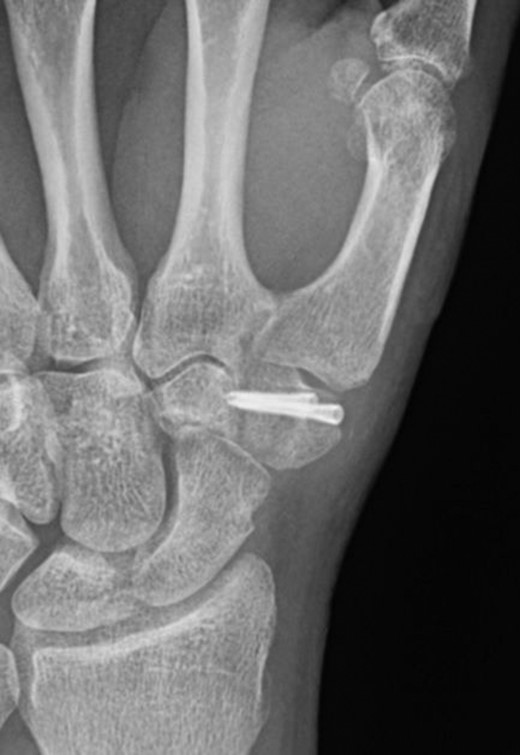

The trapezium was exposed through a Wagner approach. Intra-operatively a coronal split of the trapezium was found with no evidence of union. The fracture site was debrided, reduced and fixed with two headless compression screws. The thumb was immobilized in a plaster following surgery. Six weeks following surgery plaster was removed and the patient started physiotherapy to regain range of movement and strength. His plain radiographs at this point showed progression to union.

At 3 months from injury, the patient had complete resolution of his symptoms and had gone back to mountain biking. Range of movement had improved remarkably and he was pain free. Plain radiographs confirmed union across the fracture site (Fig. 3).